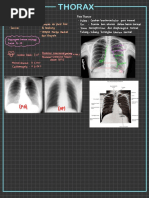

Panduan Interpretasi Foto Toraks Anak

Dokumen tersebut memberikan ringkasan singkat tentang interpretasi foto toraks pada anak dalam 3 kalimat. Dokumen tersebut menjelaskan tujuan pembuatan foto toraks pada anak, yaitu untuk melihat struktur organ dalam dada dan kelainannya untuk mendiagnosis penyakit dan memantau perkembangannya. Dokumen tersebut juga menjelaskan sistematis membaca foto toraks, mulai dari mediastinum, paru, pleura, hingga penunjang

Intrepretasi Foto Toraks pada Anak

Interpretasi foto toraks pada anak

Sinar-X dapat menembus tubuh dan memberikan bayangan sesuai dengan jaringan yang dilaluinya Tubuh akan menyerap sinar x pada berbagai tingkatan yang akan memberikan gambaran yang berbeda. Penyerapan tinggi akan memberikan gambaran putih (opak) misalnya pada tulang, penyerapan sedang akan memberikan gambaran abu-abu, misalnya pada jaringan lunak, dan penyerapan rendah akan memberikan gambaran hitam, misalnya udara. Foto toraks merupakan pemeriksaan pencitraan yang paling sering dilakukan Interpretasi foto toraks memerlukan pengetahuan dasar mengenai struktur organ normal yang terdapat di dalam rongga dada Kelainan dapat dikelompokkan atas bayangan abnormal yang berbentuk putih (opak) atau berbentuk hitam (lusen) Foto toraks memerlukan beberapa persaratan agar dapat dilakukan penilaian dengan baik

Tujuan Melihat bayangan struktur organ di dalam rongga dada serta kelainan yang ada :

Membantu dalam menegakkan diagnosis awal dan menyingkirkan diagnosis banding Melihat respons terhadap pengobatan Memantau perjalanan penyakit Melihat komplikasi yang terjadi Melihat ketepatan penempatan alat pada tubuh

Sistematika membaca foto toraks AP

Mediastinum Bayangan hilus Bayangan jantung Pembuluh darah besar Lapangan paru Pleura Diafragma Skeletal Jaringan lunak